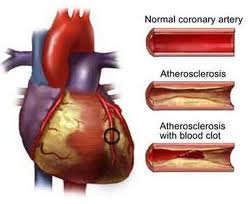

Hyperlipidaemia (or high cholesterol) is the condition in which one or more kinds of plasma lipids exist in higher than normal levels. Of these, high cholesterol and triglyceride are most common. Plasma lipids when combined with protein in the blood are water-soluble and circulate around the body. Hyperlipidemia is therefore also referred to as hyperlipoproteinemia.Lipoproteins in the plasma are divided into different types according to their densities. It is important to know the total cholesterol level as well as to measure the levels of the different kinds of cholesterol: high-density lipoprotein (HDL), also known as the ‘good’ cholesterol, and low-density lipoprotein (LDL), also known as the ‘bad’ cholesterol. The higher the density the more plasma lipids can be utilized by the body and not stored as excess, and the better the protection of the body from adverse cardiovascular events such as heart attack or stroke.

Hyperlipidemia is closely associated with diseases such as atherosclerosis, coronary heart disease, stroke, obesity, diabetes, and gall stones. It is important that the condition is treated. Education for a proper diet, exercise and use of cholesterol lowering drugs are commonly undertaken treatments.